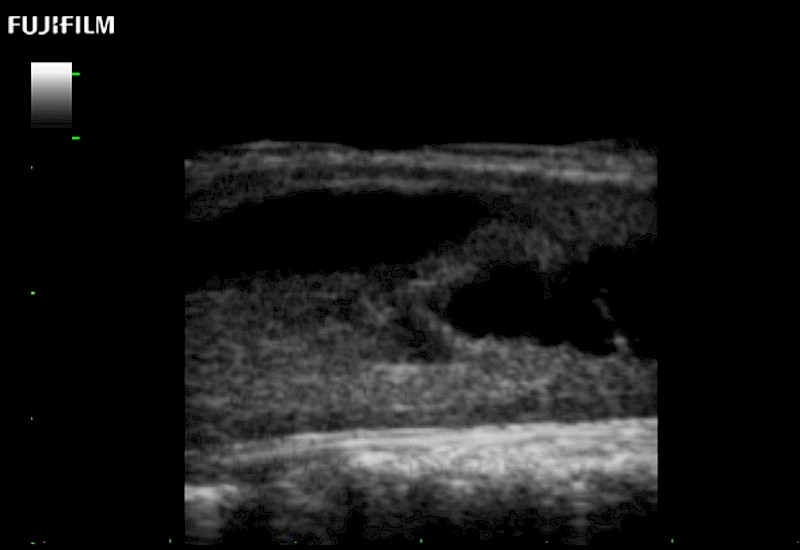

Extraordinary high-resolution digital imaging

for use during: Cranial guidance, Burr-Hole guidance, Spinal Cord guidance, Pituitary guidance, Micro-Surgery guidance